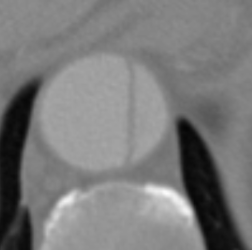

Figure 9 shows axial CTA images of an aortic dissection case. In both rows of this figure an example for executing an inpainting with the inpainting tool is given. The image section of all sub-figures is equal to the defined region of interest. The sub-figures in Figure 9 show from left to right: unedited CTA scan showing the aorta and surroundings, the mask used for the inpainting and the inpainting result. The Sub-images (a) and (b) include a dissected aorta, whereas the dissection is removed in the sub-images (d) and (f).

Refer to caption

(a) Original image

(b) Masked image

(c) Inpainting result

(d) Original image

(e) Masked image

(f) Inpainting result

Figure 9: Two examples for an inpainting of an aortic dissection utilizing the inpainting tool.

Looking at the results presented in Figure 9, one can see that the depicted dissected aorta is successfully changed to a healthy looking aorta. But it is also noticeable, that the region reconstructed by the inpainting is slightly blurred, which could be addressed by refinement of the EdgeConnect model. The timing analysis in section 6 shows that a call of the inpainting tool is completing in around four seconds, wherein the majority is caused by executing the neural network. This indicates the code of the inpainting tool itself offers little room for speeding up the application.